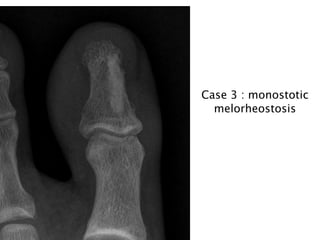

Case 3 : monostotic

melorheostosis

• 13.

Case 3 :monostotic melorheostosis

•May be monostotic or polyostotic

Sclerotic lesions of cortical bones, usually in the diaphysis,

that resemble “candle-wax-dripping”

Cortical hyperostosis with an undulating appearance usually

affecting one side of a bone